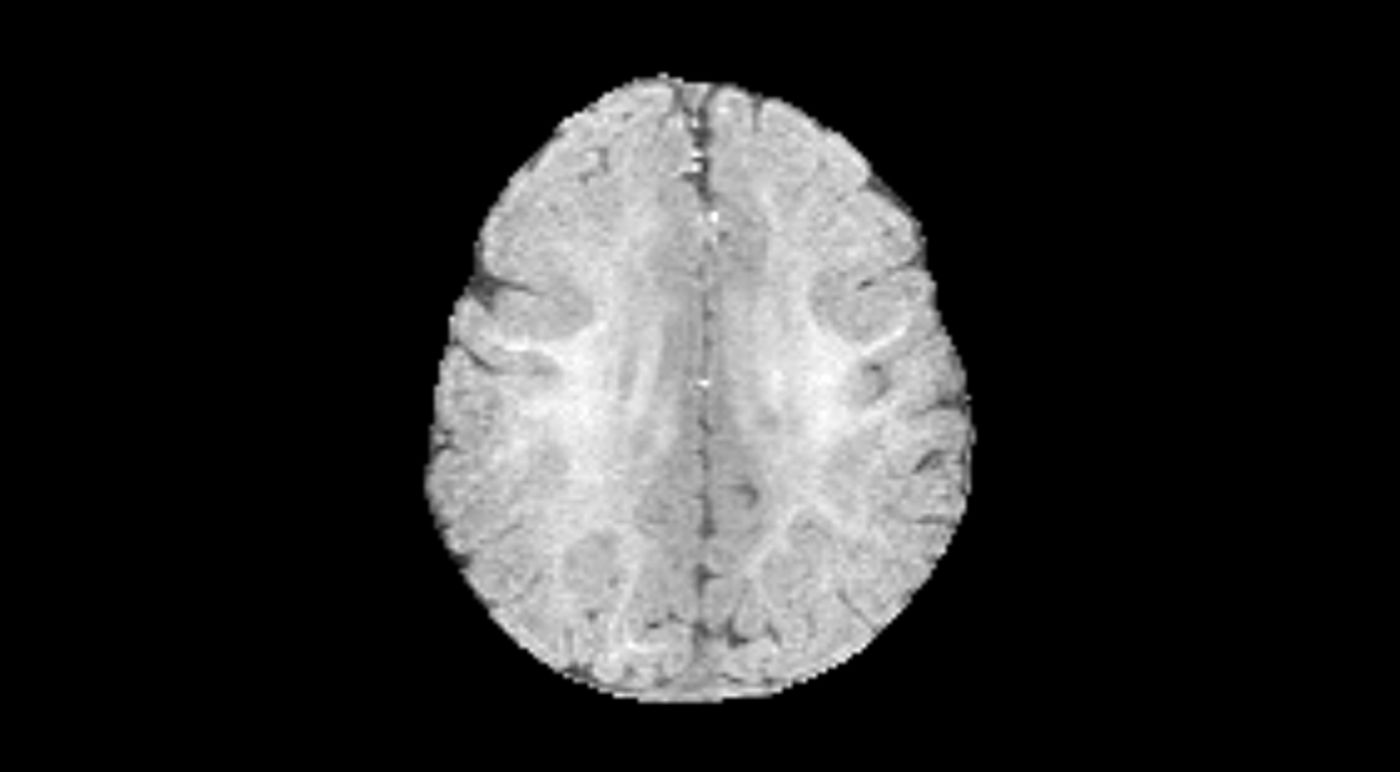

Each study is a collection of MRI images captured in different modes: T1, T2, FLAIR, and DWI. These modes highlight different tissue characteristics, helping clinicians better differentiate between various conditions (for details, see this article). To meet these requirements, this system stores additional metadata and treats multiple MRI slices as a single, unified study. This ensures that no personal data is stored on the server because we work only with an anonymized dataset.

This cut the pre-annotation time for the entire dataset, making it possible to assess the algorithm's performance on it. According to our expert radiologists, pre-annotations were useful in 40% of cases, and that alone helped reduce the manual workload. Our ML specialists also benchmarked BIBSNet’s performance in segmenting gray matter (GM) and white matter (WM) on T1-weighted (sagittal) and T2-weighted (axial) MRI scans.

As a result, pre-annotation helped us build an annotated dataset of about 750 slices. This was enough to train and evaluate machine learning models for segmentation and detection. Before running the experiments, we split the dataset into training and validation sets, using the latter to check our metrics.